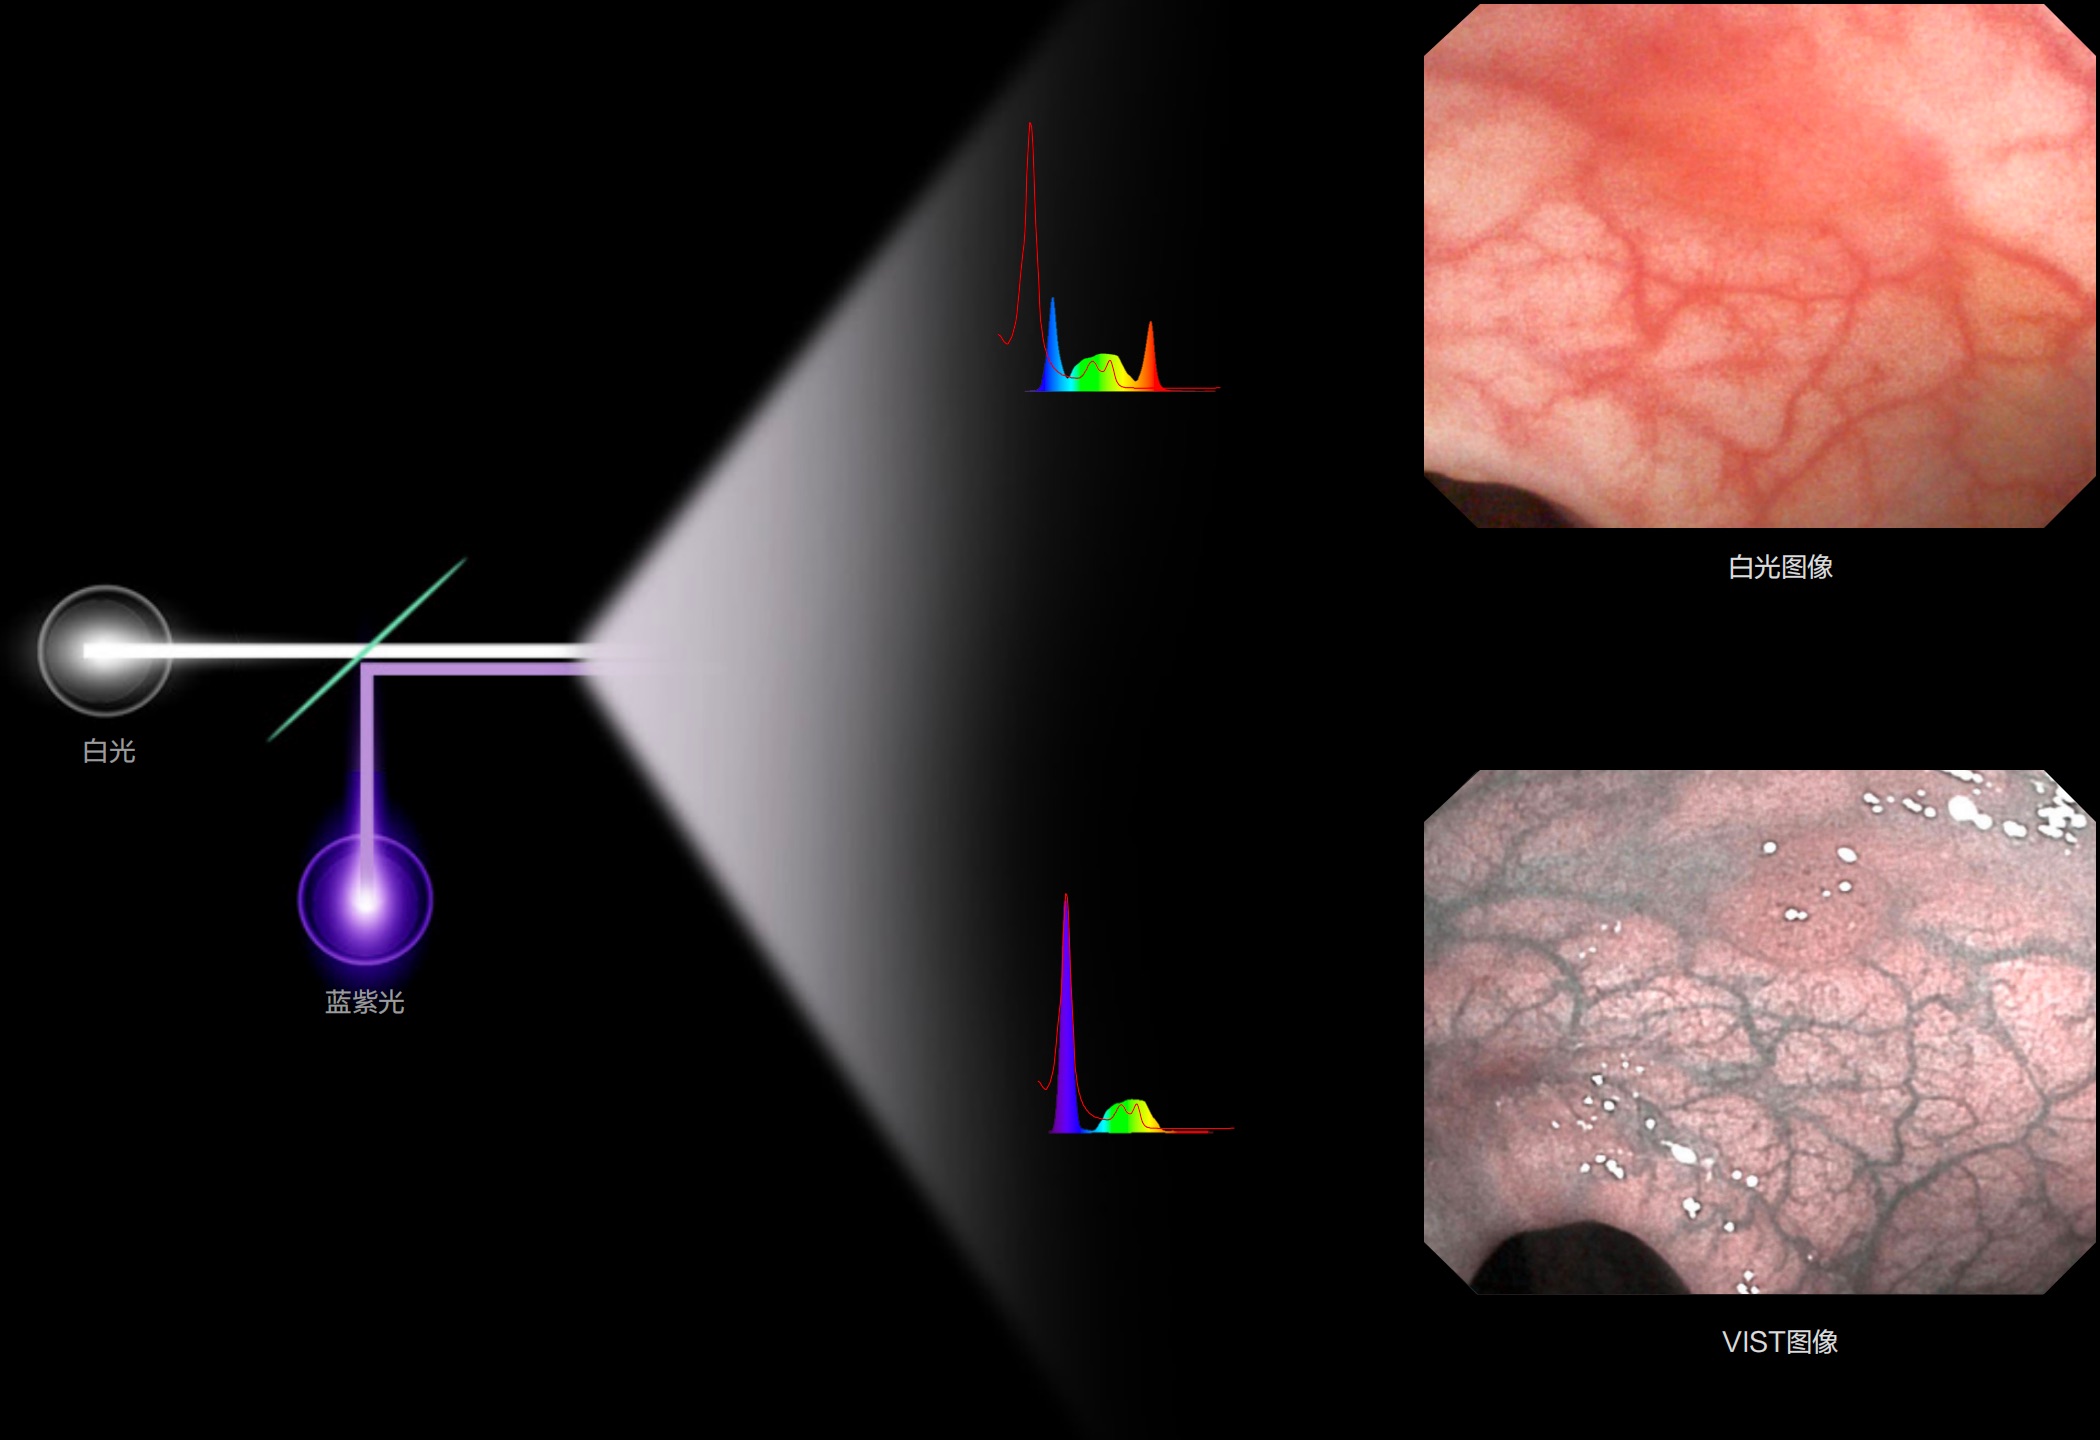

(Versatile Intelligent Staining Technology)

利用了血红蛋白在不同波长吸收下系数不同的原理,设计的一种光学域滤波和数字域滤波结合的染色技术,既保证了图像亮度,又可增强黏膜血管的对比度,充分凸显早期病变的细微结构变化,为临床疾病的观察诊断提供更丰富的参考信息。

• 白光 LED 具有高显色指数和高光通量,提供良好照明

• 蓝紫光 LED 中心波长位于血红蛋白最大吸收峰,凸显血管对比度,有助病灶识别和诊断

• 光电复合染色 (VIST),助力消化道早期疾病筛查